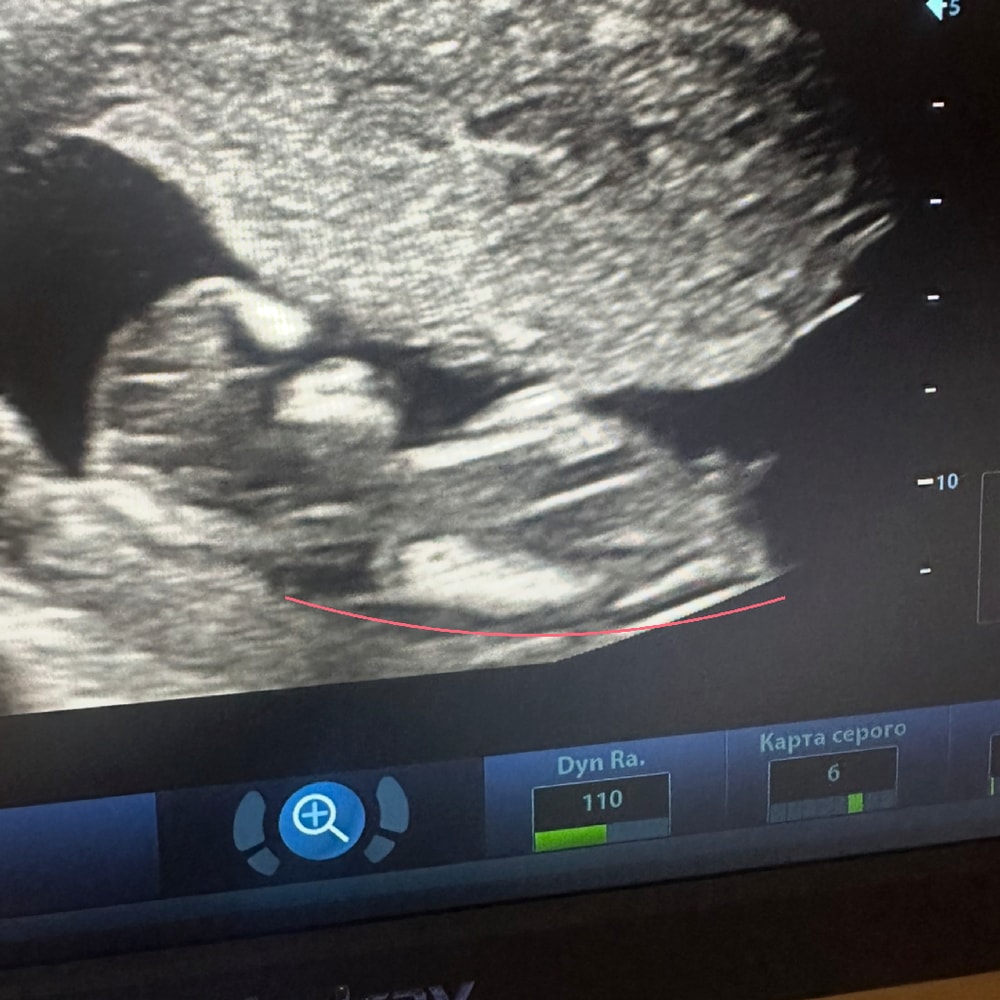

Девочки ,а кто понимает ?Помогите определить по половому бугорку

Пол малыша

Ну может предположительно кто как считаете ?)

Мне кажется у вас мадам 😻

Похоже на мальчика у вас